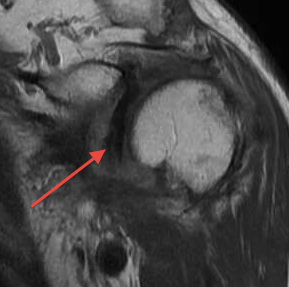

MRI

Tendonitis / tendinopathy

Normal

Tendonitis

Tendon thickening / tendinopathy

Sagittal MRI demonstrating severe LHB tendinopathy